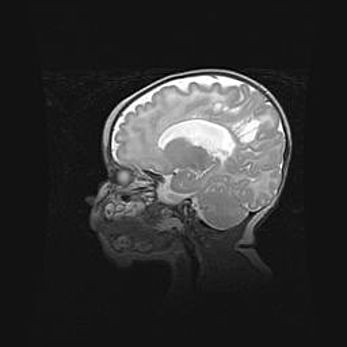

Открытая гидроцефалия.

Возраст: 9 месяцев 12 дней

Вес: 6800 г

Пол: мужской

Окружность головы: 41,5 см

Срок гестации: 28 недель

Гидроцефалия головного мозга у новорожденных имеет характерный признак: опережающий рост окружности головы приводит к визуально хорошо определяемой гидроцефальной форме сильно увеличенного в объёме черепа. Детские неврологи определяют следующие симптомы гидроцефалии у грудничков: выбухающий напряжённый родничок, частое запрокидывание головы, смещение глазных яблок к низу.